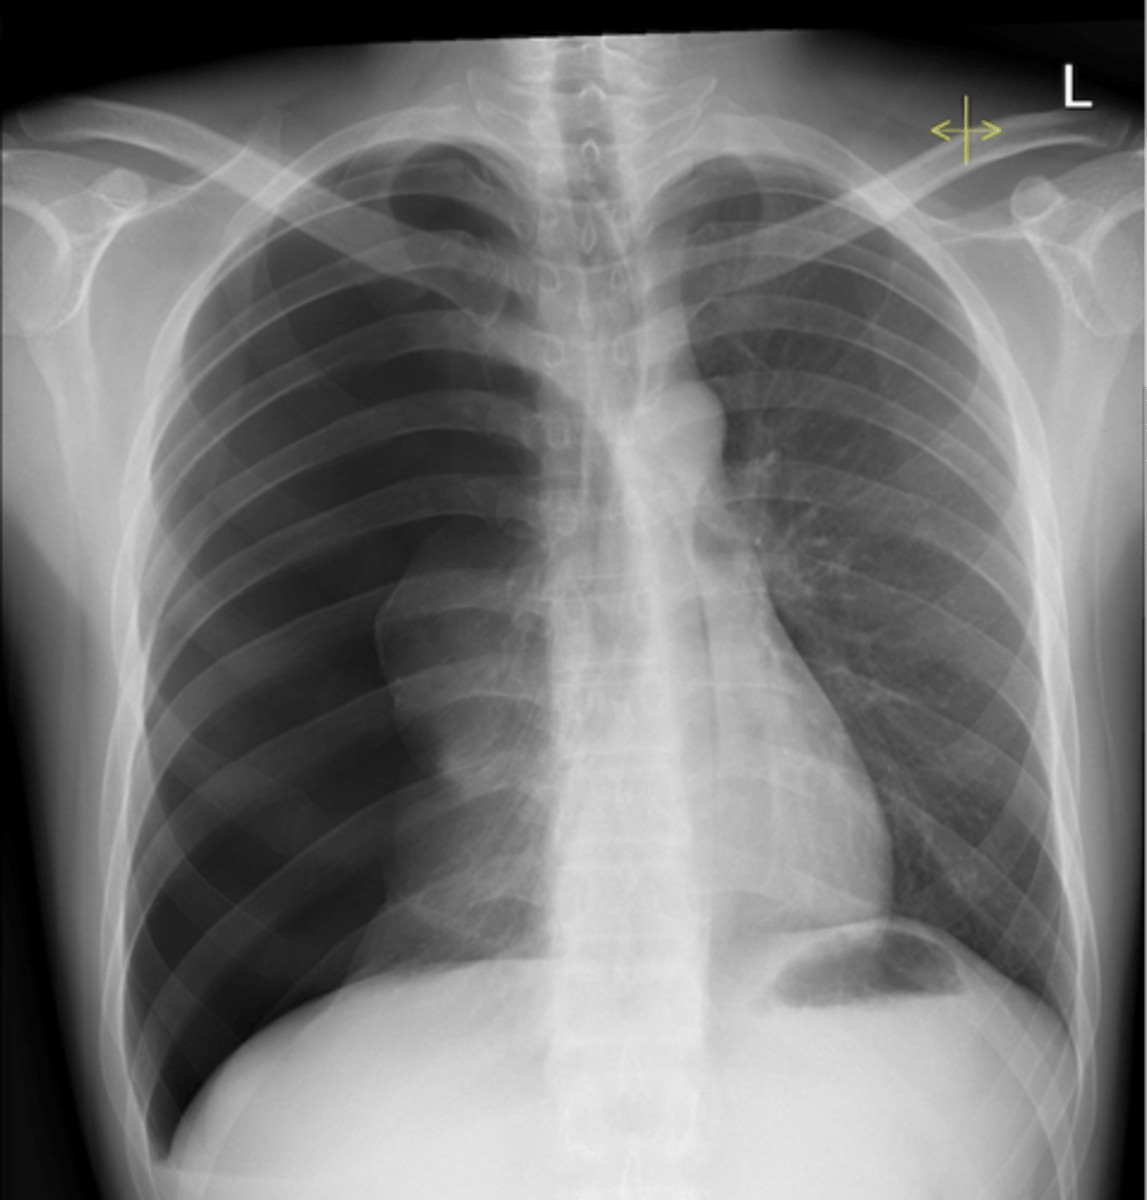

congestive heart failure

knowt flashcard image

CHF - severe alveolar infiltrate